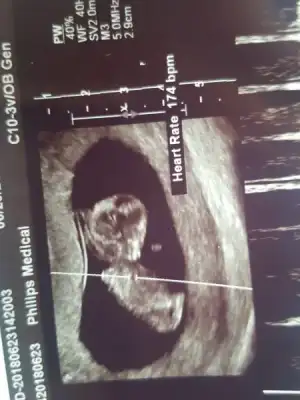

evet uyuyor gibi duruyor ayni minnos yaaa masallah cok tatliiiiBizde muayenemizi.olduk... ense kalinligina ve burun kemigine bakti cok guzel dedi..( ense 0.1 )

Bugun pek boz veremedi..uyuyordu sanirim..dr baya durttu ama pek kimildamadi .cinsiyetle ilgilide hicbisey demedi :)

gozunaydin canim.masallahBiz de bugun kontrolumuze gittik arkadaslar. Cok sukur ense kalinligi da guzel cikti, hareketleri de. Doktor cinsiyet konusunda tahminde bulunabiliriz ama kesin olmaz dedi. Ama kiz tahmininde bulundu. Cok sevindikasiri derecede stresliydim; cok sukur rahatladim. Cok heyecanli bir seymis ya